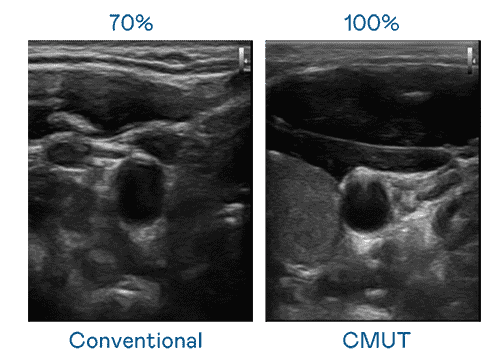

CMUT 技术是一种用电容式微机电元件来产生超音波讯号的技术。。与传统 PZT 压电式技术相比,,CMUT 频宽增加 30%,,更宽频的超音波讯号让影像解析度大幅提升,,,,是实现高影像品质医疗超音波扫描、、、促进精准医疗发展的关键技术。。。

大频宽带来超清晰影像

超音波影像的解析度高低,,首先取决于探头能发出的讯号频宽。。。。牛牛游戏 CMUT 可提供高清晰的超音波讯号,,提供高频宽、、、、高灵敏度、、、影像纹理细节更高的超音波影像,,,,协助医护人员缩短影像判读时间及利用精准的医疗影像进行诊断。。。。